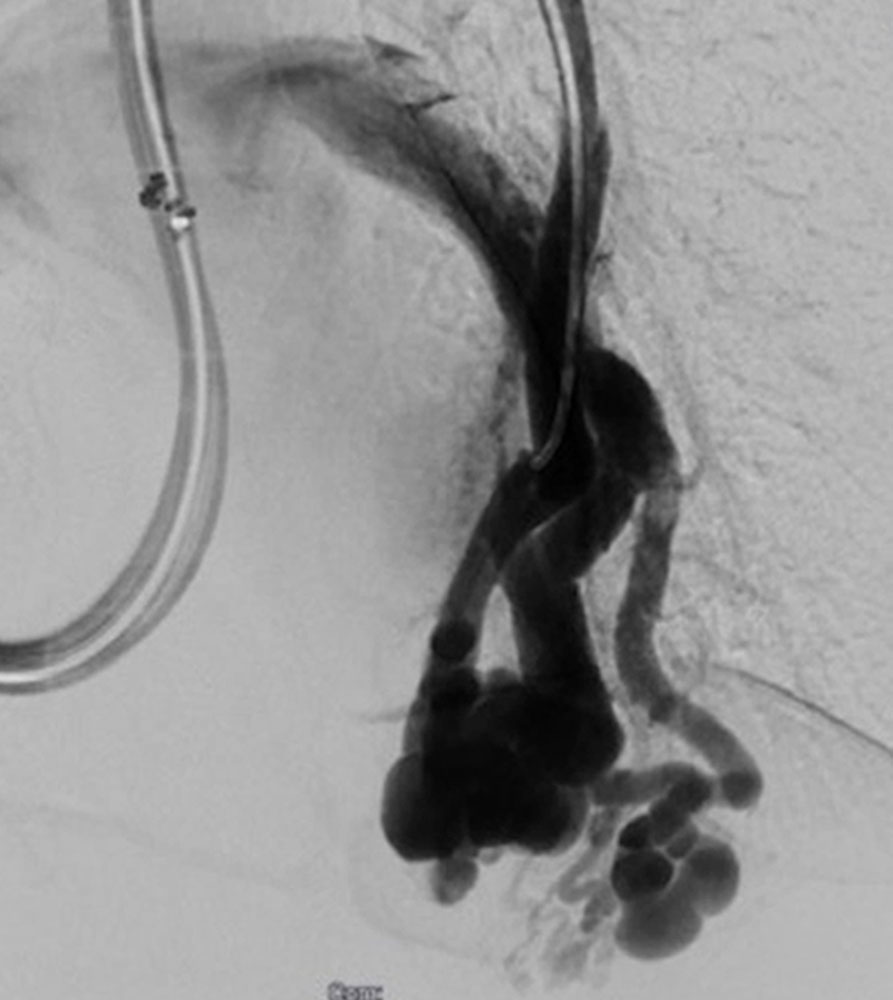

Shunts of the liver (arteriovenous, arterioportal, portosystemic) are routinely investigated by ultrasonography and, if necessary, Doppler sonography. CT, MRI, and catheter angiography complement the diagnostic workup when the suspicion of clinically relevant shunts is confirmed and the diagnosis needs to be more precise.